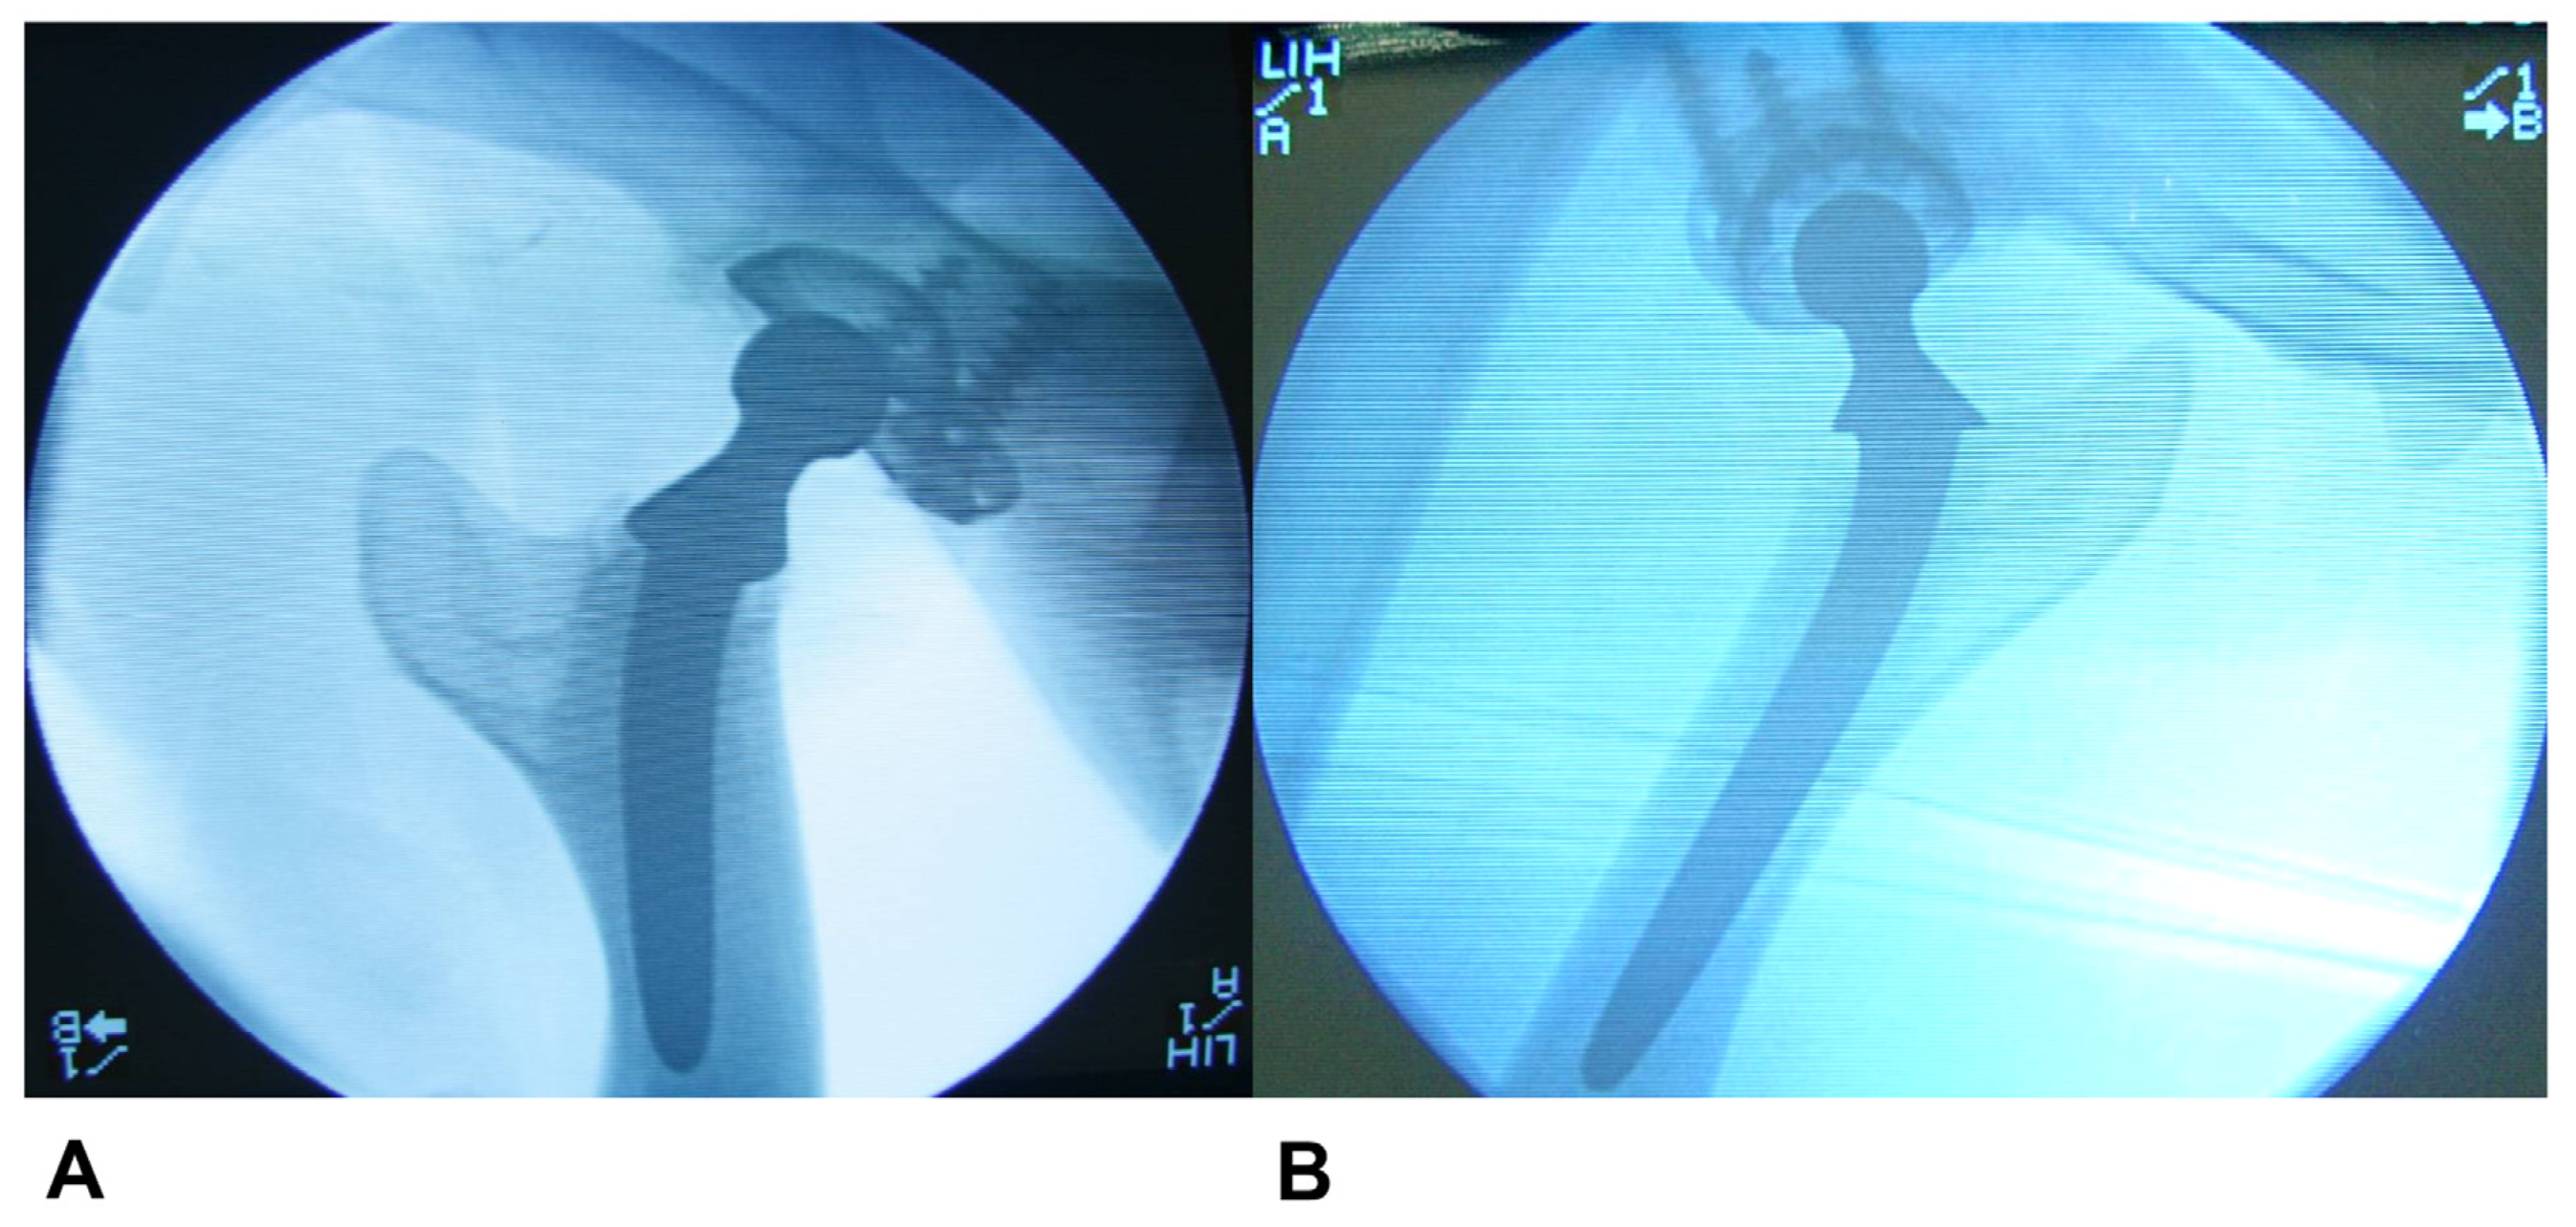

Macroscopic, Microscopic, and Radiological Evaluation